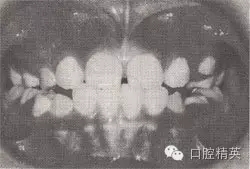

患者,女,10歲,替牙頜。磨牙近中關(guān)系。前牙反頜,下頜前突。下頜體稍長,下頜位置前移,上頜前頜骨區(qū)發(fā)育稍差。

診斷:安氏Ⅲ類前牙反猞,骨性Ⅲ類,毛氏Ⅱ¹。

矯治設(shè)計:面罩前牽引上頜,移下頜位置向后,抑制下頜生長??趦?nèi):全牙弓夾板,后牙平面頜墊式活動矯治器。矢狀關(guān)系調(diào)整后,去掉前牙區(qū)夾板,雙曲舌簧加力移切牙向唇向。

治療時間:2個月,上頜前移,下頜位置后移,切牙覆猞、覆蓋正常。

圖8-44 安氏Ⅲ類錯頜,混合牙列前牙反頜矯治前后面頜像

矯治前面相

矯治后面相